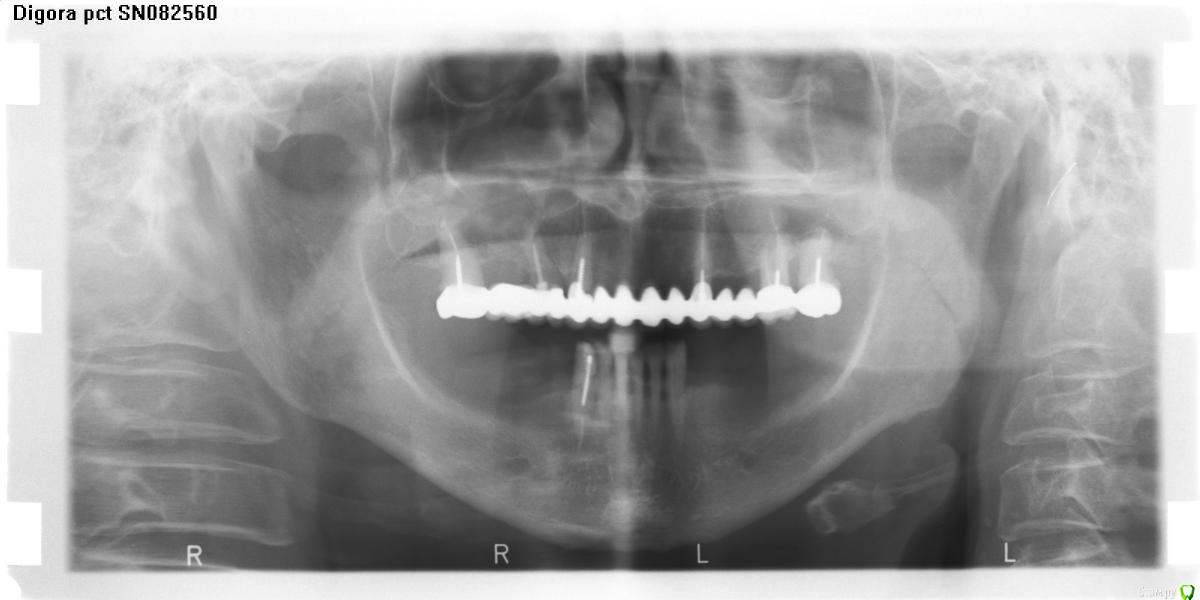

jsvc Опубликовано 17 апреля, 2017 Поделиться Опубликовано 17 апреля, 2017 Здравствуйте. подскажите пожалуйста. На очередном осмотре стоматолог сказал имеется воспаление между 42 и 43. Надо удалять 42.Предыстория такова: год назад перелечен 43 и поставлена вкладка+коронка как опора под бюгельный протез.Что-то не согласен с удалением. Мне кажется что причина воспаления в 43 (произошел скол стенки корня + нависающая коронка).Можно ли как-нибудь вылечить данную ситуацию и сохранить 42 и 43? Ни 43 ни 42 не болят.Заранее спасибо за ответ.Приолжение: панорамный февраль 2016 (качество правда никакое)прицельный март 2017 Ссылка на комментарий

колесников Опубликовано 17 апреля, 2017 Поделиться Опубликовано 17 апреля, 2017 Оптг до протезирования 43? У Вас ещё проблемные 32,31. Надо в комплексе решать. Ссылка на комментарий

jsvc Опубликовано 18 апреля, 2017 Автор Поделиться Опубликовано 18 апреля, 2017 (изменено) Да, ОПТГ перед протезированием год назад. В ходе протезирования установлена коронка+вкладка на 43 и коронка на 33. На них опирается бюгельный протез. Но что делать с воспалением между 43 и 42?Про 32 и 31 врач при осмотре ничего не сказал. Изменено 18 апреля, 2017 пользователем jsvc Ссылка на комментарий